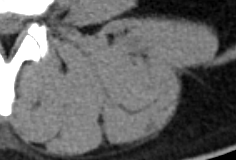

CT상에서 보이는 회색 근육이고, 검은색지방이다. 좌측 사진을 보면 근육 사이사이 검은색 선이 보이는데 지방이다. 물론 사람에서는 그렇고, 소고기에서 이 지방마블링이라 한다.

등심은 복벽 밖에 있고, 길고 두꺼우며, 기름이 많다. 반대로 안심은 복벽 안에 있고, 얇고 가늘며, 기름이 적다. 운동으로 등심(ecector spinae muscle, 척추 기립근)은 부피를 키울 수 있지만, 안심(psoas muscle, 요근)은 키우기 어려워 육질이 훨씬 부드럽니다.